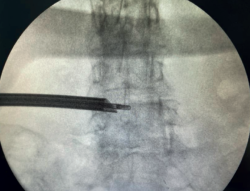

Figure 3. Radiological view of ipsilateral single-portal transforaminal endoscopy. As can be seen, the access allows easy reaching of the midline.